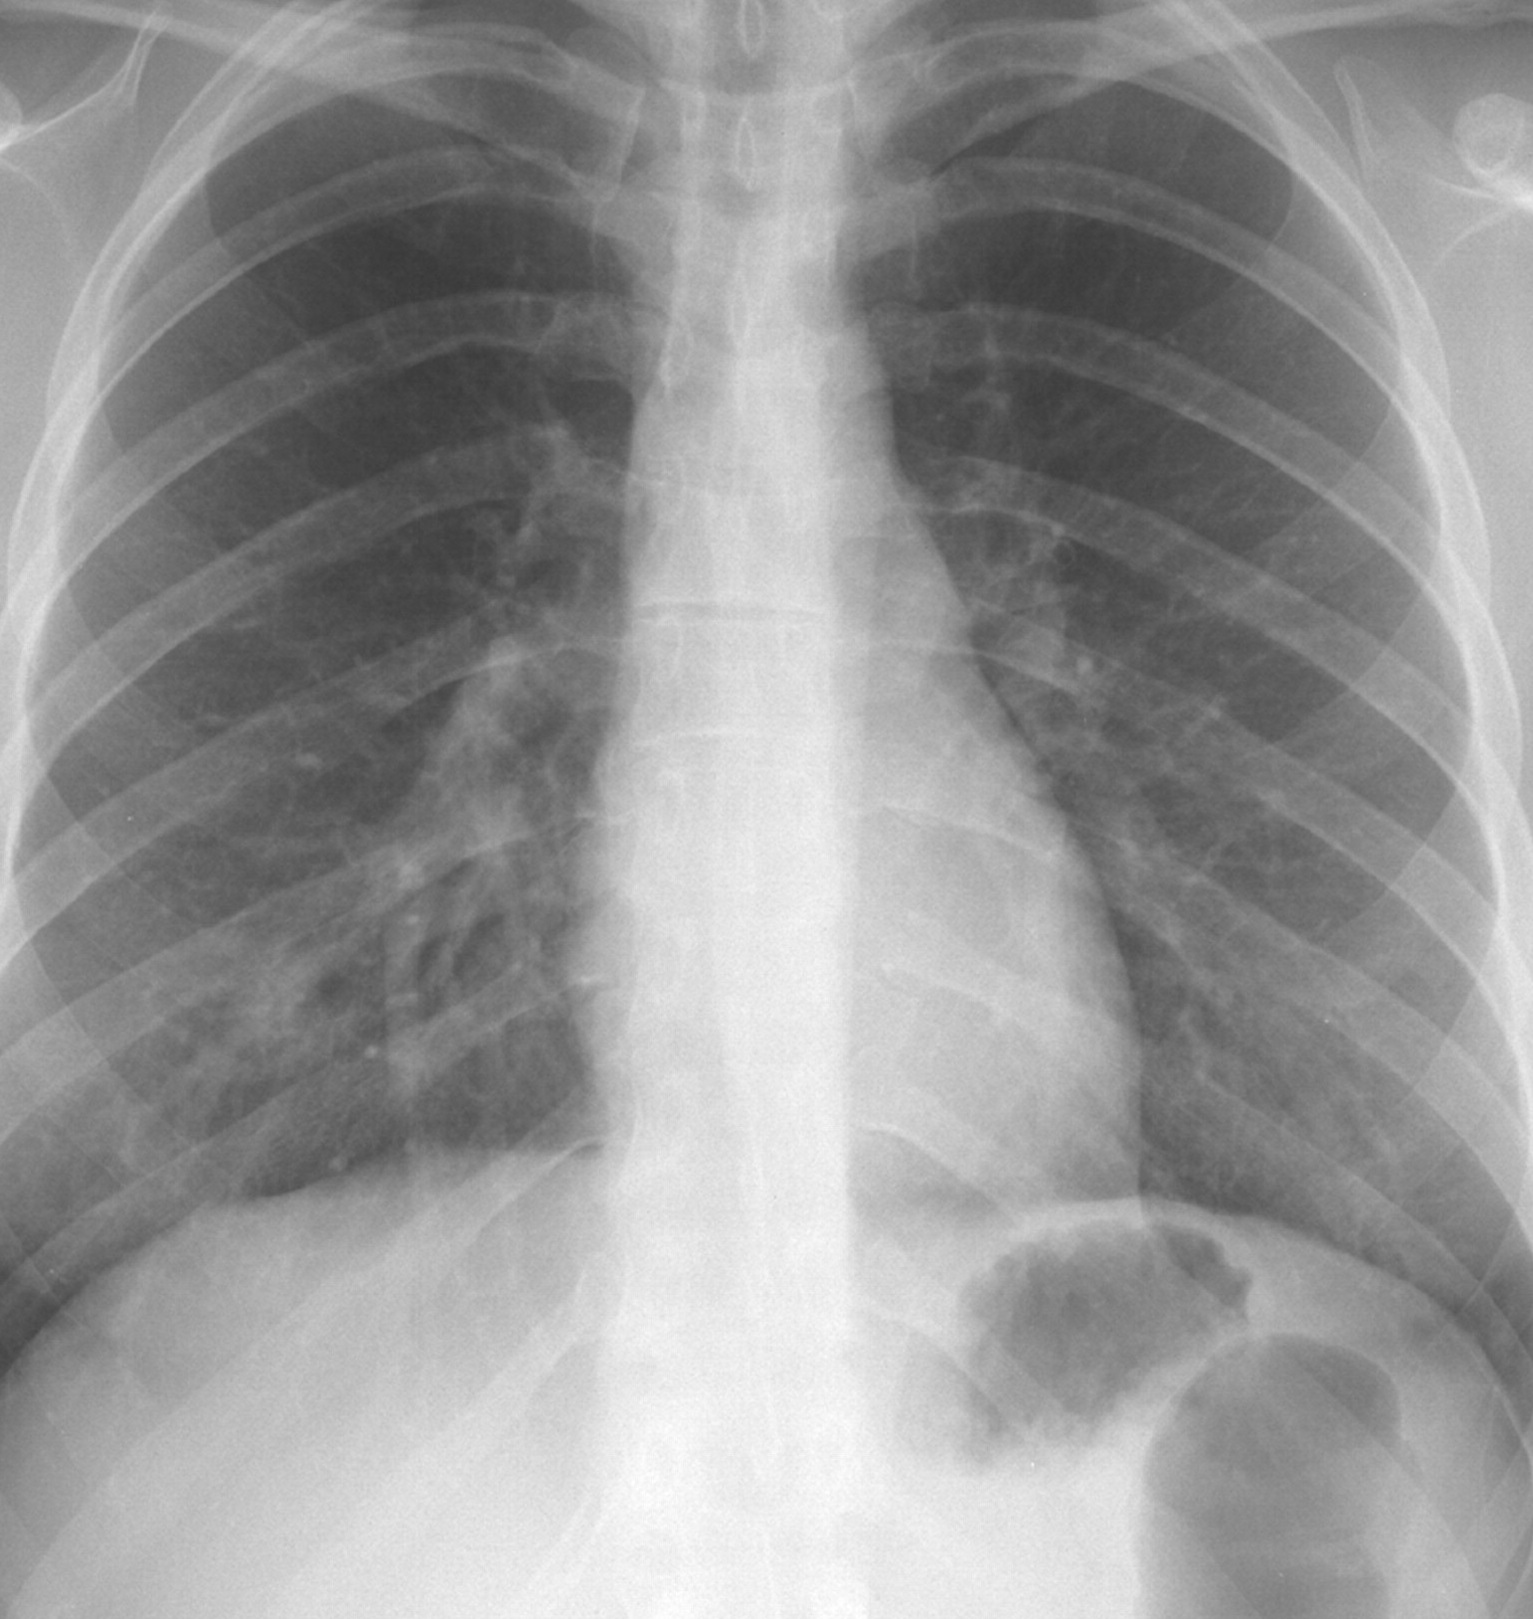

Figure 6 presents image examples for each class retrieved from the RYDLS-20 database. It is worth to mentioning that we have no further information concerning the CXR images with regarding the CXR machine used to take the image, as well as the origin, age and ethnicity of the people whose these images belong to.

Refer to caption

(a) Normal.

(b) COVID-19.

(c) SARS.

(d) MERS.

(e) Pneumocystis.

(f) Streptococcus.

(g) Varicella.

Figure 6: RYDLS-20 image samples.